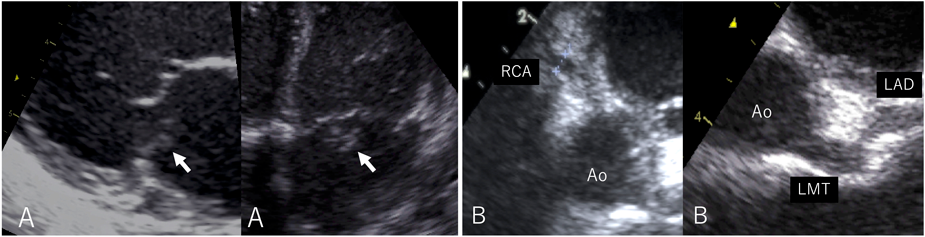

On admission, the body temperature was 36.7°C. A systolic heart murmur, gallop rhythm, and hepatomegaly were confirmed. On the chest radiograph, the cardiothoracic ratio was 50%, and pulmonary congestion was noted. Severe mitral regurgitation due to ruptured chordae tendineae of the posteromedial leaflet was diagnosed using echocardiography (Fig. 1). Aneurysmal dilatation of the proximal coronary artery was also observed. The left main coronary artery was 3.7 mm (z score 5.83), the left anterior descending artery was 3.0 mm (z score 5.30), and the right coronary artery was 3.1 mm (z score 6.13). Laboratory investigations suggested leukocytosis (25,000/µL), thrombocytosis (131×104/µL), hypoalbuminemia (3.1 g/dL), and elevated C-reactive protein level (6.30 mg/dL). Based on the coronary arterial lesion and laboratory data, we diagnosed her with ruptured mitral chordae tendineae due to severe valvulitis resulting from incomplete Kawasaki disease.

Fig. 1 Transthoracic echocardiography

(A) Severely prolapsed posterior leaflet of the mitral valve (arrow). (B) Coronary artery lesions in the left main coronary trunk (z score 5.83), left anterior descending artery (z score 5.30), and right coronary artery (z score 6.13) Ao, aorta; LAD, left anterior descending artery; LMT, left main coronary trunk; RCA, right coronary artery.